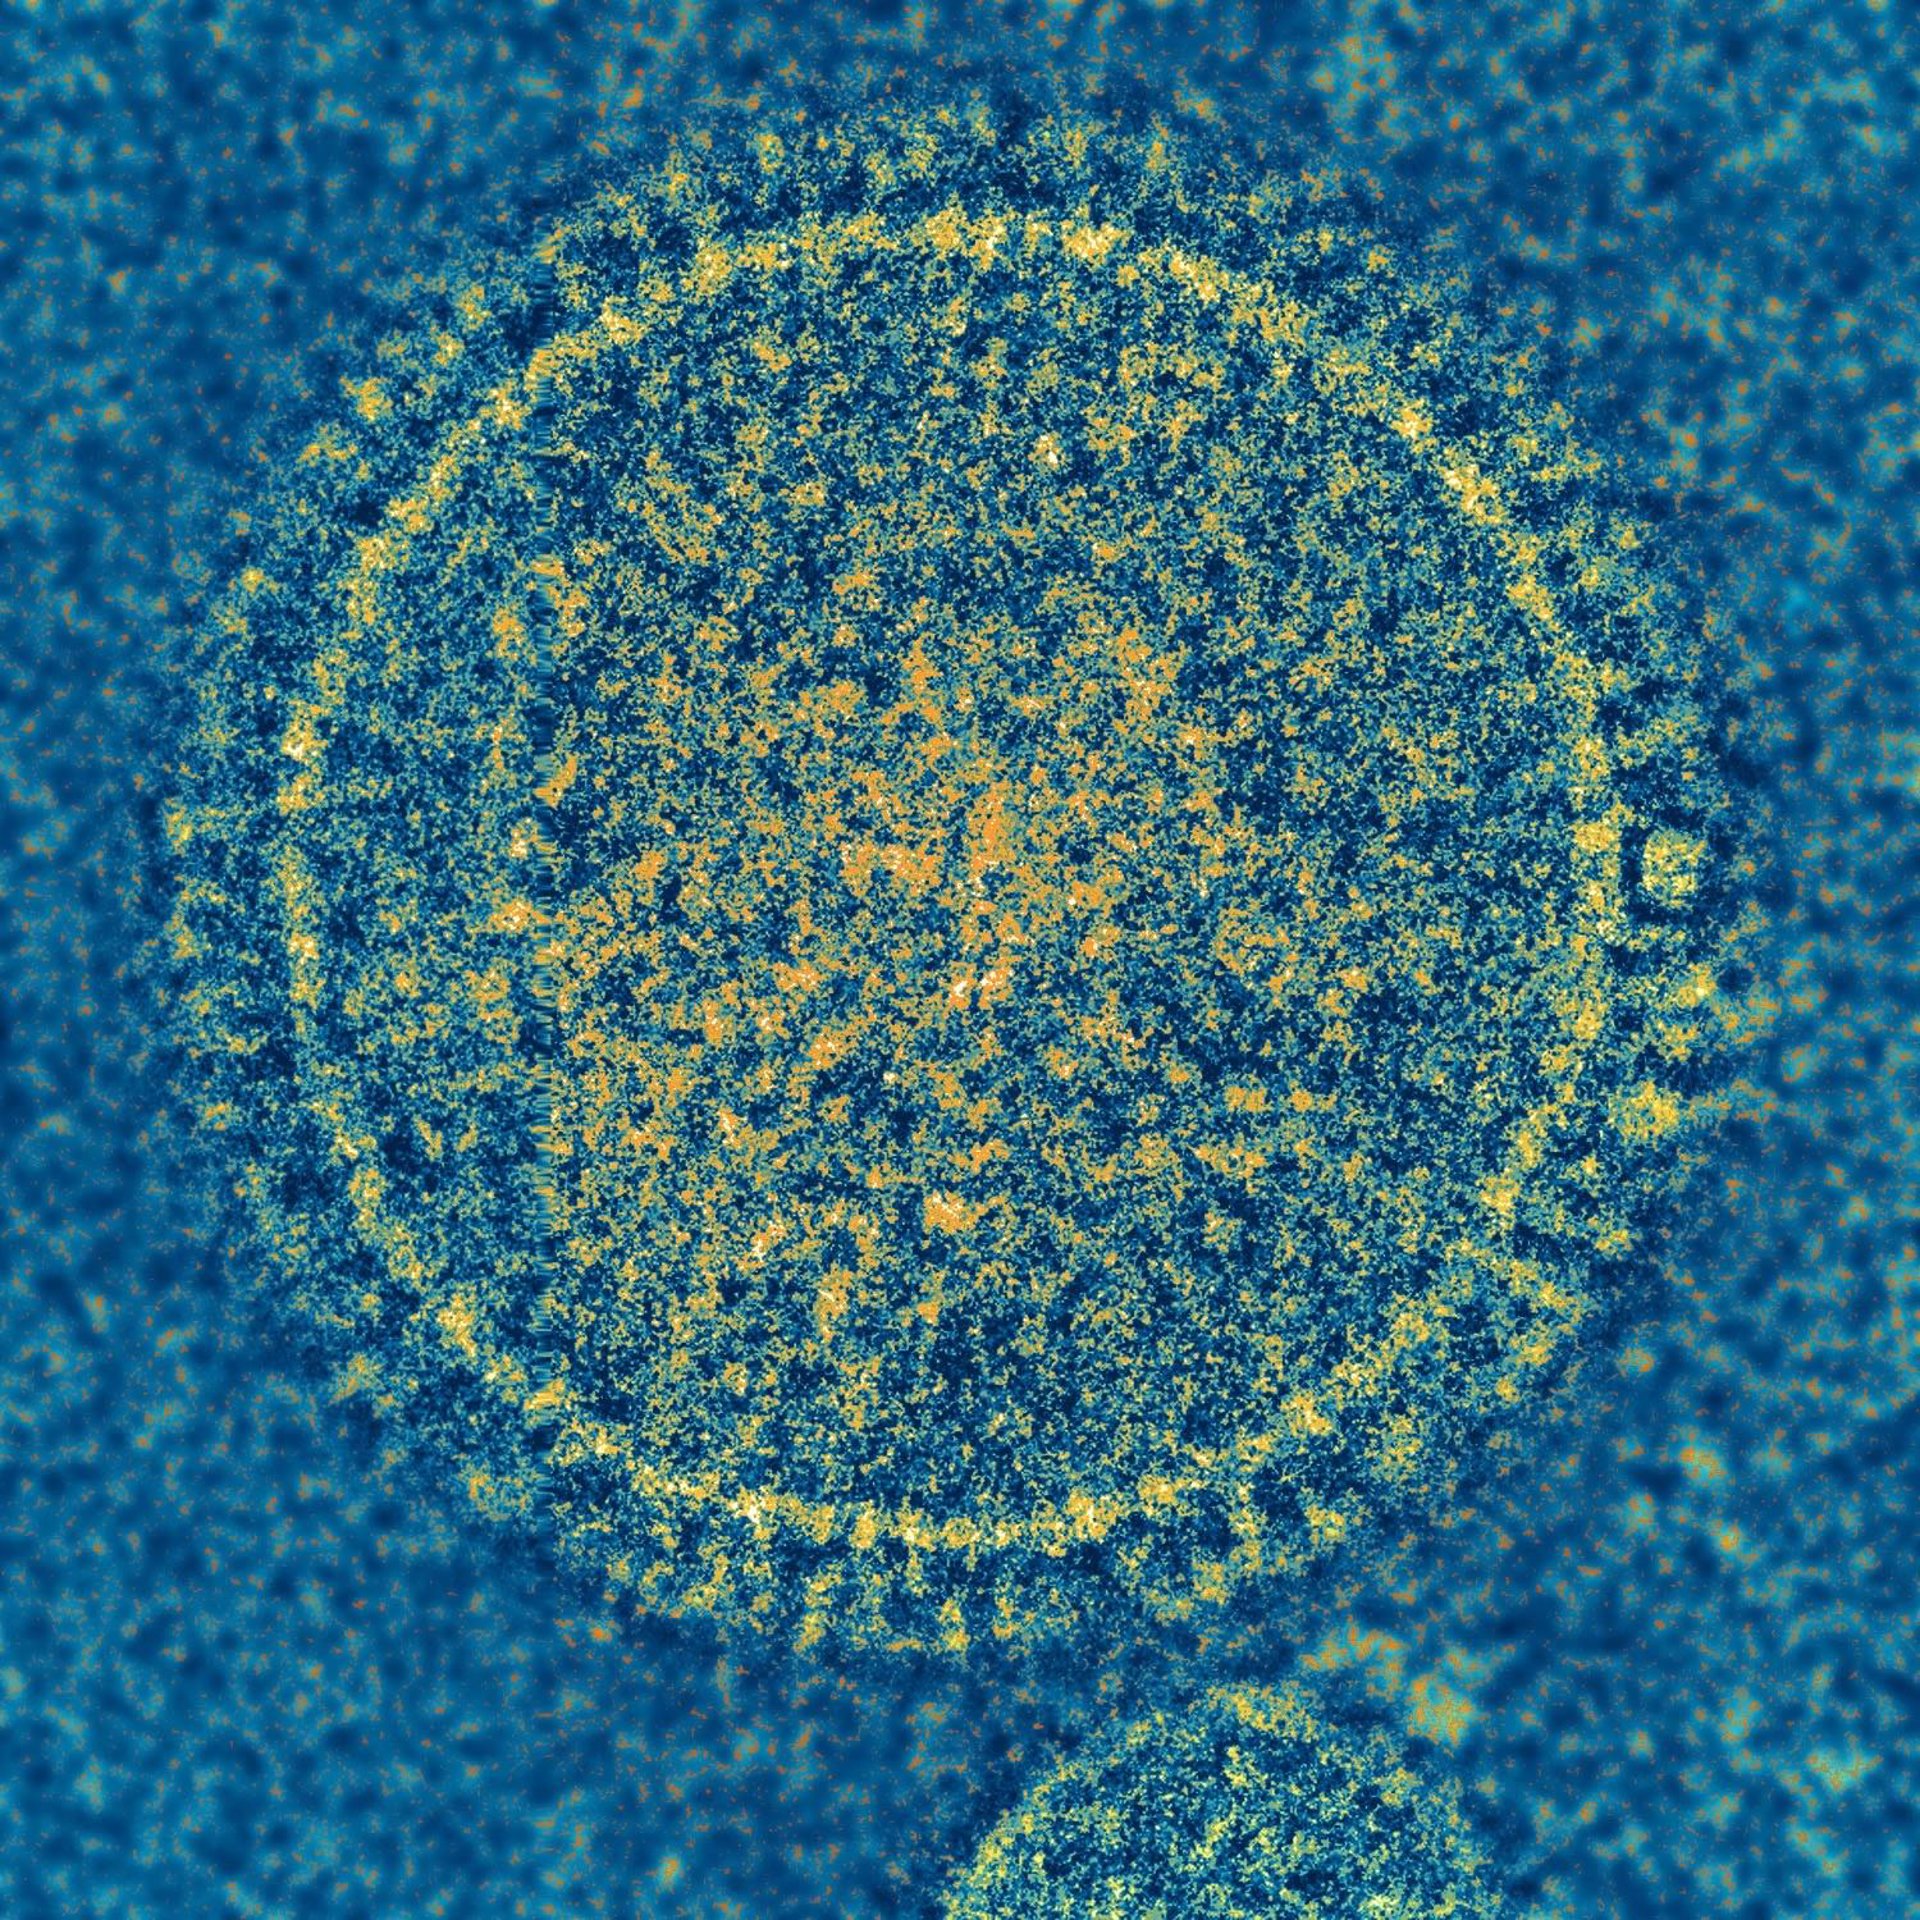

Virus sincitial respiratorio

NIAID